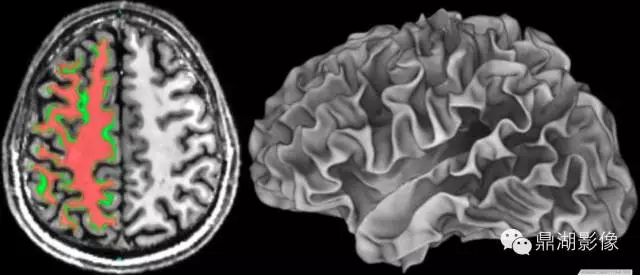

1.磁体系统:磁共振技术发展离不开磁体技术的进步,随着高场强磁体的应用,磁共振技术也进入了功能影像的时代。美国FDA已批准全身3T系统用于临床。4T系统已得到FDA无明显危险的许可。已在7T系统上对几百例健康志愿者完成无事故和无明显安全危险纪录的测试。在9.4T系统上对成年兔及其后代未观察到不良的生物效应。11T、12T系统也早已进入科研。目前磁共振的空间分辨率甚至可以达到0.2毫米的水平,清晰度可以是普通CT的5倍。另外,为了患者检查的舒适度及适应一些特殊类型人群的要求,更大口径的磁体(70cm大孔径磁体)也开始在临床普及。

我们可以清晰的发现12T明显对脑白质损伤更加敏感